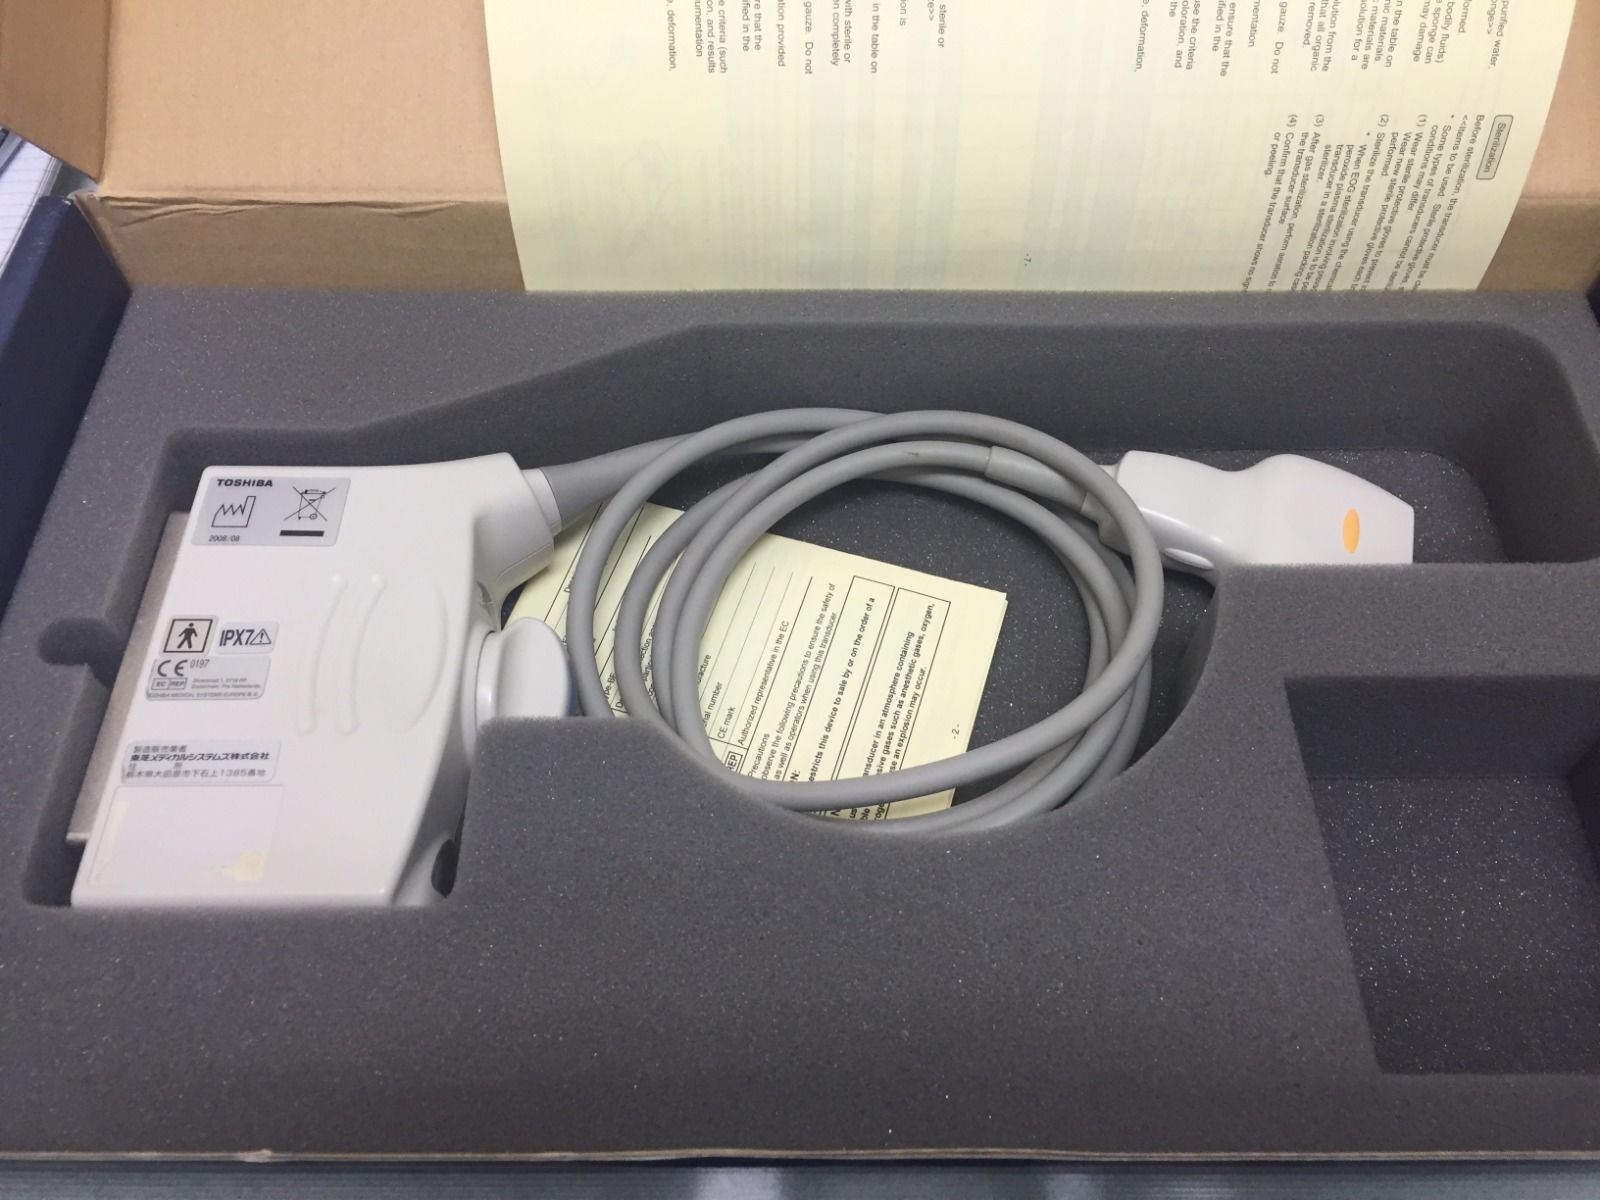

Toshiba Probes

DIAGNOSTIC ULTRASOUND MACHINES FOR SALE